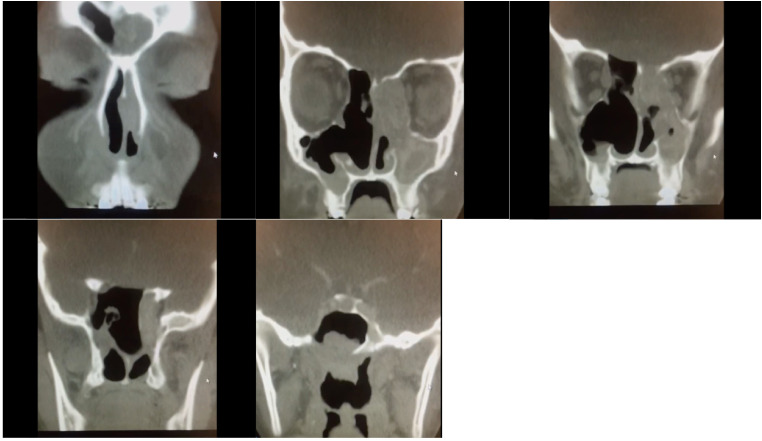

Allergic fungal rhinosinusitis (AFRS) is a subtype of chronic noninvasive sinusitis accounting for 7.8% (0.2%-26.7%) of all chronic rhinosinusitis cases. A definitive diagnosis is usually made after sinus surgery. Successful treatment requires a combination of surgical and medical management. Although orbital involvement is relatively common, reports on optic neuropathy and acute vision loss are limited. Herein, we present a series of 3 patients with AFRS who presented with acute visual loss as the chief complaint. All 3 patients were otherwise healthy adults in their early 20s with extensive nasal polyps on endoscopic nasal examination and bone erosion in the bilateral orbits and lateral wall of the sphenoid sinus on the affected side on imaging. One of the 3 patients had bilateral cranial nerve IV defects in addition to cranial nerve III defects. All patients underwent endoscopic sinus surgery with orbital decompression and were followed up postoperatively by both otolaryngology and ophthalmology services with endoscopic and radiologic evaluation. Unfortunately, no meaningful improvement in vision was observed in any patient despite successful nerve decompression. Prompt diagnosis and early medical and surgical intervention are warranted to prevent complications in patients with AFRS with orbital extension.

Abstract Image